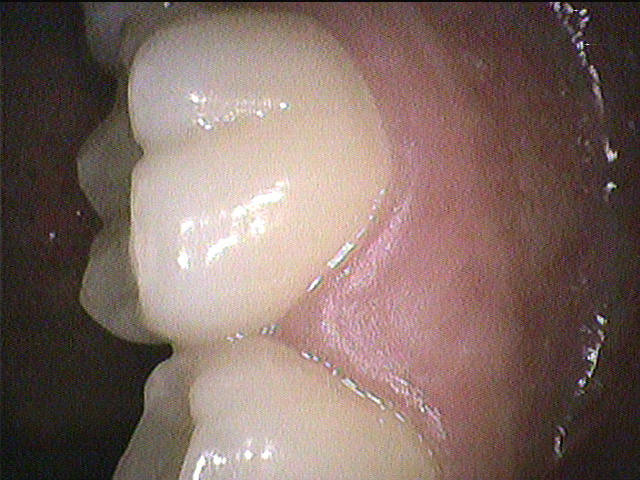

◎クリーニング前 右上奥歯の表側

◎クリーニング後

奥歯の根元は歯ブラシが当たりづらく、磨き残しやすいところになります。

奥までしっかりと歯ブラシの毛先が当たるように気を付けながら、時間をかけて丁寧に磨きましょう!

さらにタフトブラシを使って仕上げ磨きをすると良いです😊